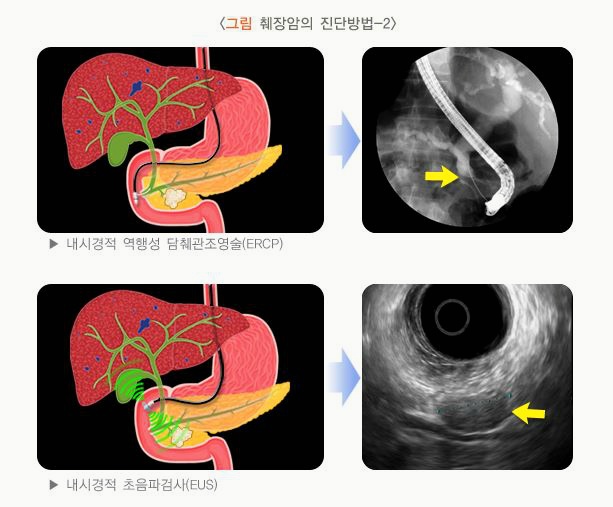

- 내시경 초음파(EUS), ERCP: 필요 시 시행

- 췌장암 검사방법

- 내시경 초음파(EUS), 조직검사